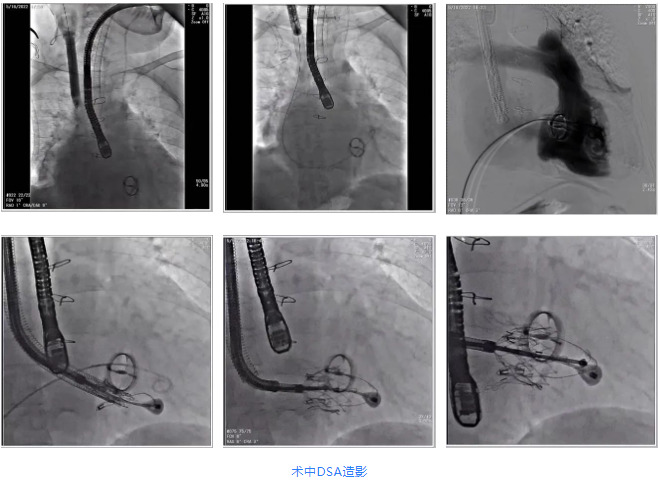

根據(jù)術(shù)前評估結(jié)果,郭應(yīng)強(qiáng)教授團(tuán)隊為患者量身定制了手術(shù)策略,決定使用LuX-Valve Plus經(jīng)血管三尖瓣置換系統(tǒng)開展手術(shù)治療。手術(shù)在全麻下進(jìn)行,采用經(jīng)右側(cè)頸靜脈入路,在經(jīng)食道超聲和DSA的指引下調(diào)整輸送器角度以達(dá)到正確位置,勾住前瓣后逐步釋放盤片,盤片打開后順利扎針,最終完成瓣膜植入,輸送器撤出。術(shù)后超聲提示人工三尖瓣同軸性良好,瓣架固定牢靠,無反流和瓣周漏,術(shù)后三尖瓣平均跨瓣壓差為1 mmHg。